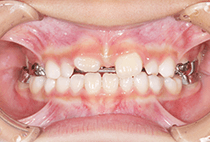

20代女性の患者さま。

八重歯の見た目が気になってご来院されましたが、実は顎の痛みや開口障害など、顎関節症の症状もありました。

そのため、かみ合わせと顎関節症の治療を同時に行ったにもかかわらず、2年間で治療が終了。

かみ合わせが整い咬筋の過緊張も改善しました。咬筋の肥大も治ってフェイスラインがすっきりしました。

最終的には美しい歯並びと、安定した痛みのないかみ合わせが実現しました。

八重歯が気になる

叢生、顎関節症、開口障害

20代女性

矯正治療2年

24回

唇側矯正

矯正:1,161,600円+毎月調整量:6,050円

しっかり前歯を下げるために、インプラントアンカーを使用してコントロールしました。

かみ合わせが整うと咬筋の過緊張が改善。

過緊張による筋肉肥大も改善しフェイスラインもすっきりしました。

治療前

治療後